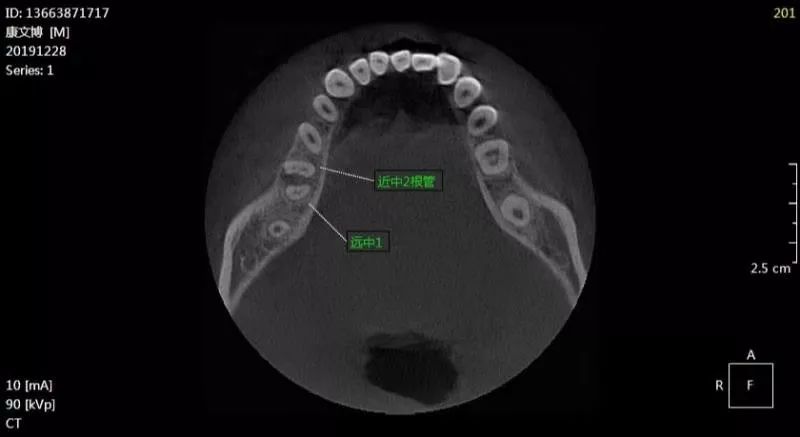

康xx2019122846根尖周炎ct136xxxx1717

图片尺寸800x437